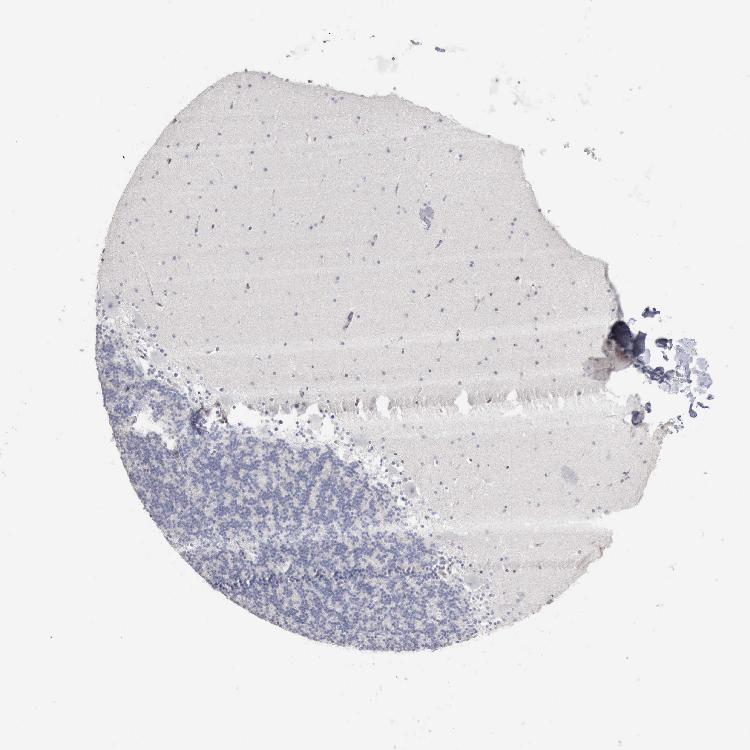

CEREBELLUM - Antibody stainingi

Antibody staining in the annotated cell types in the current human tissue is reported as not detected, low, medium, or high, based on conventional immunohistochemistry profiling in selected tissues. This score is based on the combination of the staining intensity and fraction of stained cells.

Each image is clickable and will lead to virtual microscopy that enables deeper exploration of all samples and also displays staining intensity scores, fraction scores and subcellular localization as well as patient and tissue information for each sample.

Antibody HPA000931Antibody HPA000982Antibody CAB004049

Purkinje cells Not detectedNot detectedNot detected

Cells in granular layer Not detectedNot detectedNot detected

Cells in molecular layer Not detectedNot detectedNot detected